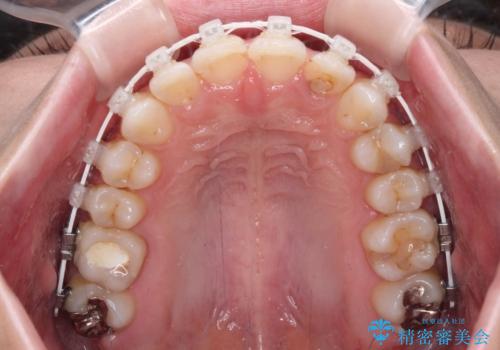

- 歯並びと虫歯をきれいにしたいとのことで来院された患者様です。

楽して短期間で歯列を整えたいとのことで、ワイヤー装置を用いて矯正治療を行い、矯正治療後に下顎の虫歯はセラミックインレー、上顎はPGAインレー(ゴールドインレー)、根管治療を行う歯についてはオールセラミッククラウンにて補綴治療を行うこととしました。

矯正治療は8ヶ月ほどで終了し、速やかに虫歯治療に移行することができました。

保険治療で用いる樹脂(コンポジットレジン)で行った虫歯治療は、周辺が変色して汚くなっていましたが、下顎はセラミックインレーで審美的に、上顎はPGAインレーで歯に負担の少ない治療を行うことができました。